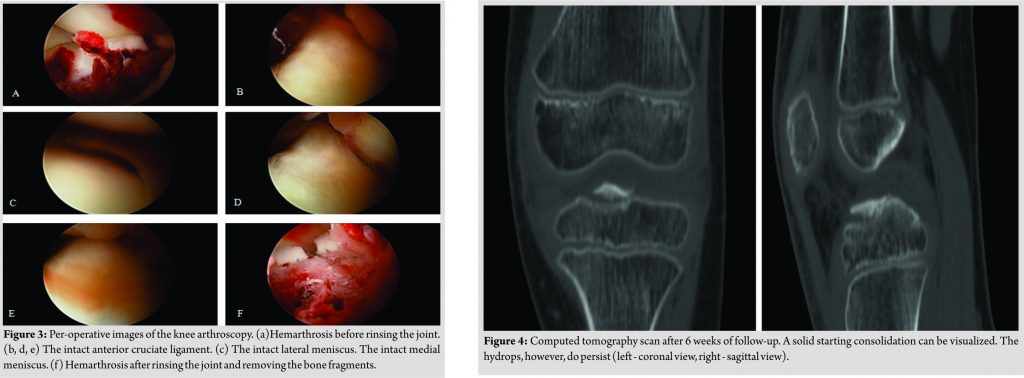

A male Caucasian 8-year-old child presented at the hospital’s emergency department in Belgium. The circumstances of the accident were reported as a fall on the left knee complicated by a contact trauma with another child. At consultation presenting, complaints were a sharp pain in his left knee and difficulties to walk. The pain was scored as 4/10 on the visual analogue scale. In clinical examination, anterior pressure pain, swelling, and a restricted range of motion(flexion up to 100° and extension deficit of 5°) were the main findings. Performing ananterior drawer test and Lachman test, no laxity was documented. On conventional anteroposterior and lateral view of the X-ray, a minimal displaced fracture of the intercondylar eminence, two loose bone fragments, and a bloated suprapatellar bursa indicating hemarthrosis could be evidenced (Fig. 1). A CT scan confirmed a fracture of the intercondylareminence (Fig. 2).

The fracture was classified as Meyers and McKeever Type II [4]. The initial treatment provided an adequate pain management with appropriate analgesics and plaster immobilization in 0–5° of flexion. Based on the clinical and radiological findings, a knee arthroscopy was performed 3daysafter injury. The indication for arthroscopic surgery was removal of the intra-articular bony fragments and to evaluate whether the fracture was stable. The fracture of the proximal tibia was visualized through arthroscopy (Fig. 3).

The ACL was still intact yet showed a discrete laxity. No other fractures or injuries were visualized. Furthermore, the joint was rinsed and the loose bone fragments were removed to improve thee xtension and deep flexion. Peroperatively, the ROM was tested and was complete. Postoperatively, the knee was immobilized in extension with a hard cast. Weight-bearing was not allowed. Physiotherapy was established to strengthen and stabilize the knee. In the first follow-upconsultation 1 week after surgery, a new hard cast was applied for one more week. The patient was instructed to continue the isometric exercises for adequate revalidation. After 2 weeks of cast immobilization, an extension brace was applied for another 2–3 weeks. 6 weeks after the initial trauma, clinical examination showed a positive clinical course. A follow-up CT scan was performed (Fig. 4) that could show a starting consolidation. A CT scan examination was discussed with the family of our patient since his wish was to start sporting (football) early. Furthermore, CT scan is superior to X-ray with the disadvantage of a higher radiation dose. The extension brace was removed and a soft walking brace was applied. The patient was allowed to walk by full weight-bearing, taking pain and stability into account. A T1-weighted magnetic resonance imaging (MRI) scan was performed at 8weeks of follow-up (Fig. 5).This examination was initially performed because of a new trauma and was ordered by the general practitioner. However, it is useful to present the result of the MRI in this case report. The MRI showed an almost complete consolidation alongside very limited edema of the bone (Fig. 5a and b). The ACL and posterior cruciate ligament (PCL)weretotally intact (Fig. 5c and d). Clinically, the knee showed normal stability. The walking brace was permanently removed, and the patient was allowed to perform routine daily activities including all sportive activities. No more follow-up consultations were planned.